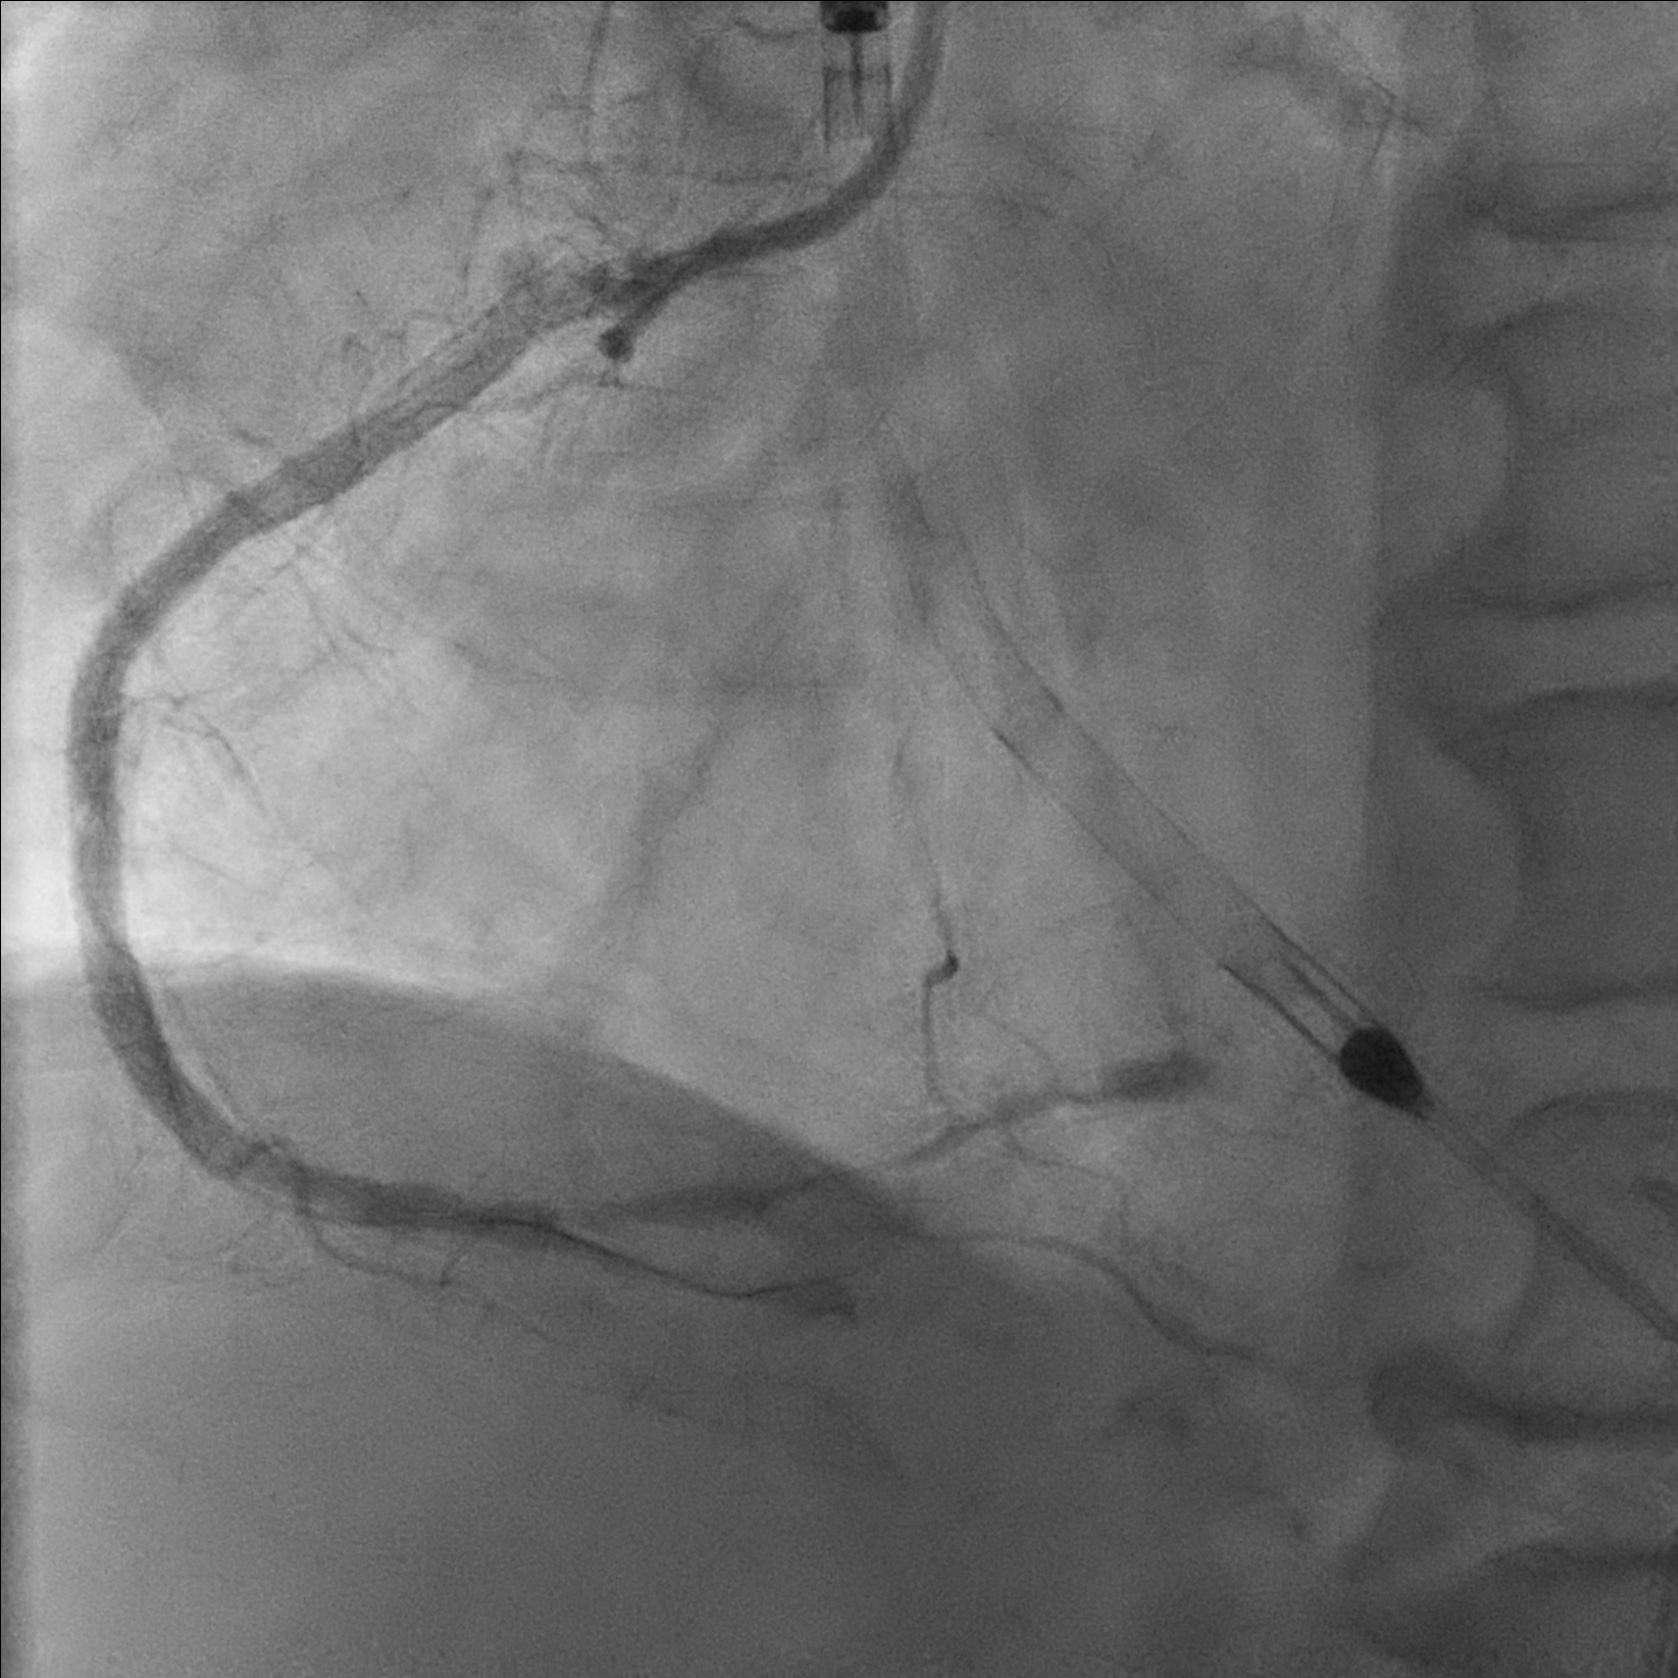

Developed diminishing arterial waveform. Angiogram showed TIMI 1-2 flow, retrograde injection showed no retrograde filling. IVUS showed subintimal hematoma, suspected distal dissection. Hematoma covered with a 4.0/14 DES. IVUS showed good stent apposition and no edge dissection. Flow improved to TIMI2-3 flow after intracoronary adenoscan and adrenaline. Noted filling defect over mRCA stent. Intracoronary integrillin was given and stent thrombosis resolved angiographically.

Impella assisted PCI showed be considered in patient with high risk anatomy and poor LVEF.

Differential diagnoses of no reflow including microvascular dysfunction, intravascular obstruction and flow competition.

Rapid identification of complication is important for prompt management.